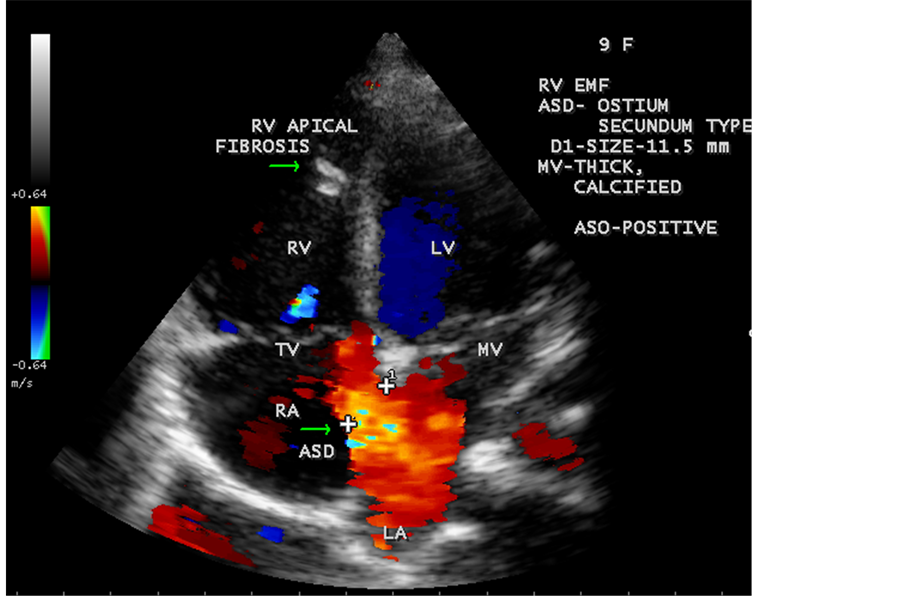

Figure 64. RV EMF associated with ostium secundum atrial septal defect with rheumatic mitral valve involvement in a 9-year-old female with positive serum ASO titer (anti-streptolysin O).

Figure 65. RV EMF with ASD (atrial septal defect) in a 9-year-old female.

ventricle”) in a 16-year-old female as shown in Figure 50 to Figure 53 were detected. RV EMF with rheumatic involvement of mitral valve as shown in Figure 54 and Figure 55 in a 44-year-old female and in Figure 63 in a 55-year old female. Biatrial enlargement due to rheumatic atrioventricular (AV) valves (mitral and tricuspid) involvement characterized by stenosis of the valves are illustrated in Figure 56 to Figure 59 in a 54-year-old female and it is differentiated from EMF which is characterized by AV valve regurgitation as shown in Figure 34 and Figure 60. RV EMF associated with thickening and fibrosis of moderator band in a 16-year-old female was shown in Figure 46. RV EMF associated with apical left ventricular hypertrophic cardiomyopathy was shown in a 47-year-old male as in Figure 61 and in a 65-year-old female as in Figure 62.